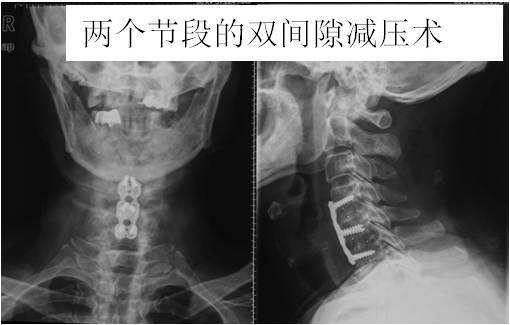

神经根型颈椎病和大多数脊髓型颈椎病可采取从脖子前面开刀(颈椎前入路),如椎间隙减压术(图6,图7),椎体次全切除术(图8)。

这种手术方式的特点是:手术微创,切口3—4公分(图9),切口美容,出血少(一般100ml),恢复快,术后1—2天可戴颈托下地行走。但对手术的技术要求较高。